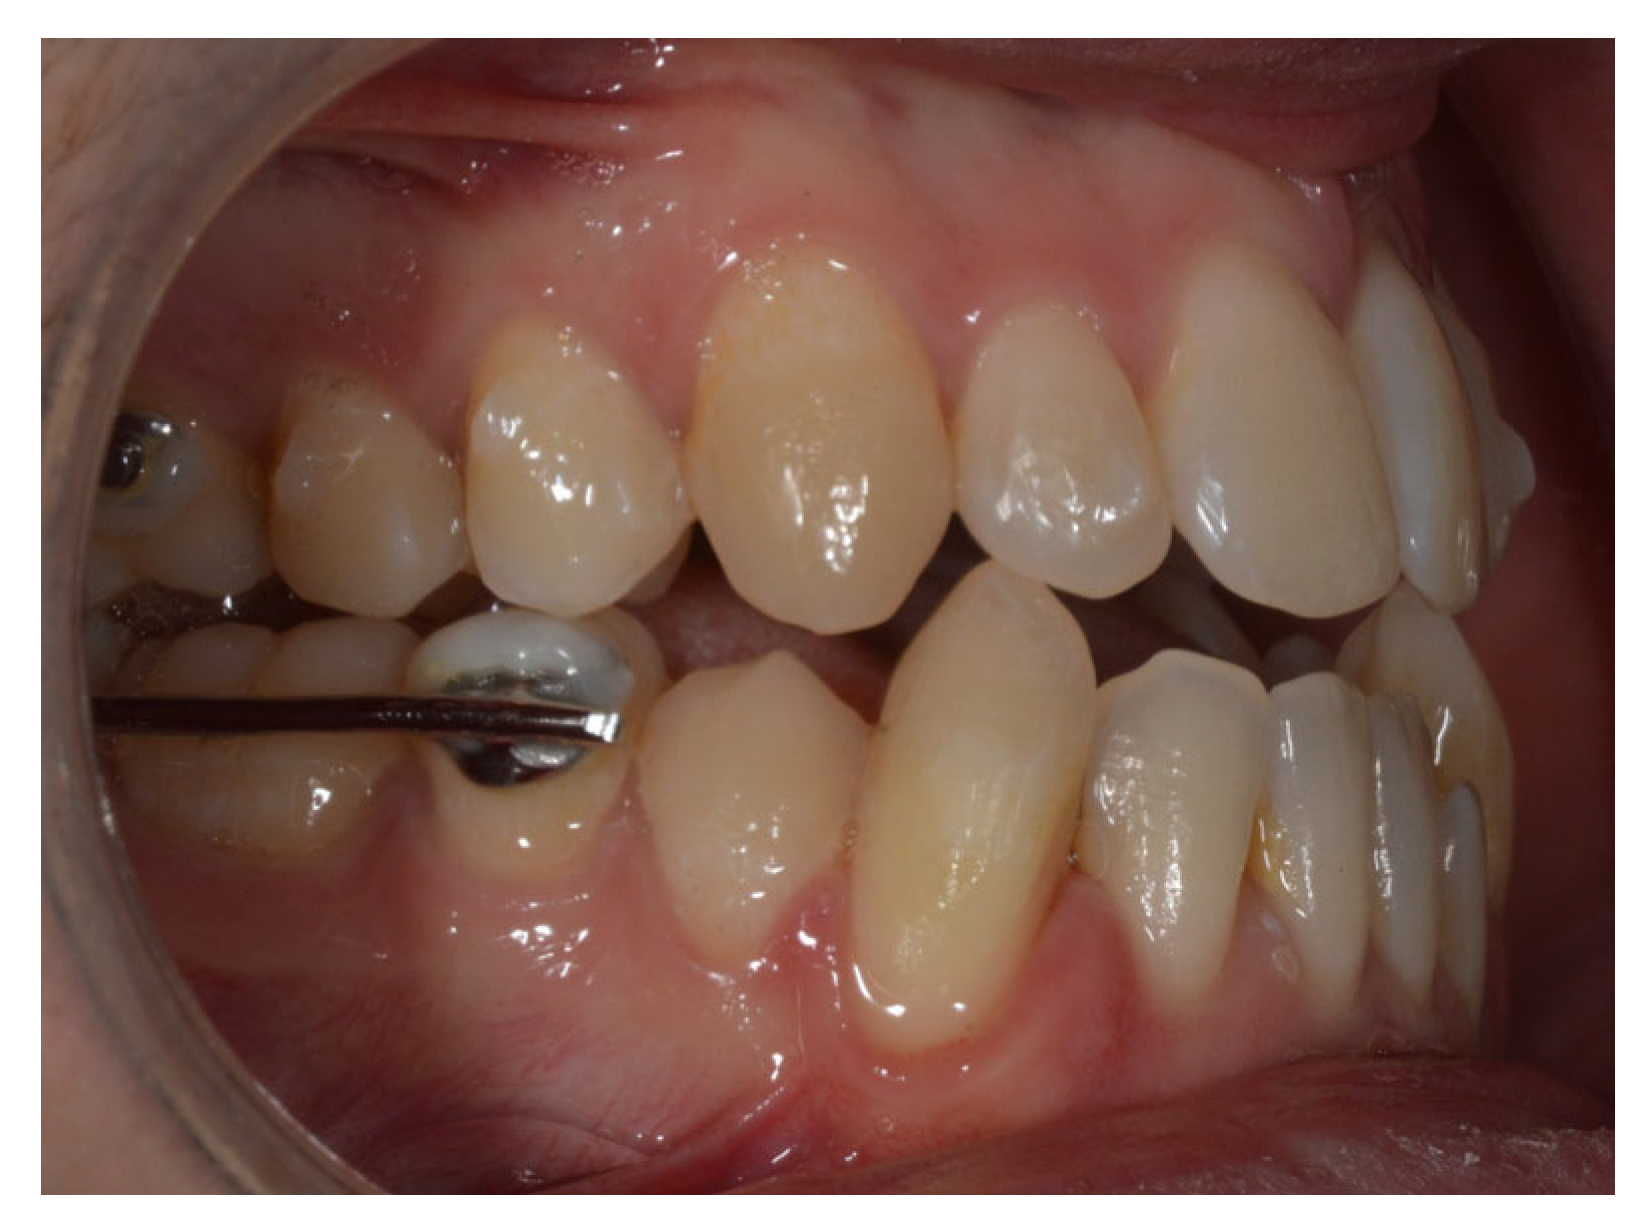

Due to persistent difficulties in extruding the lower left lateral incisor during the initial full set of lower aligners and the lack of response after a second attempt (refinement), a hybrid approach was adopted. A sectional fixed appliance was placed from the lower left canine to the lower right canine using conventional brackets to facilitate the extrusion of the lower left lateral incisor, a movement that had proven ineffective with aligners alone in this case (Figure 4). Concurrently, ¼″, 4 oz Class III elastics were maintained to reinforce sagittal corrections and minimize relapse risk.

Figure 4. Changes in the vertical position of the mandibular incisor (32) achieved through hybrid treatment involving the use of brackets.